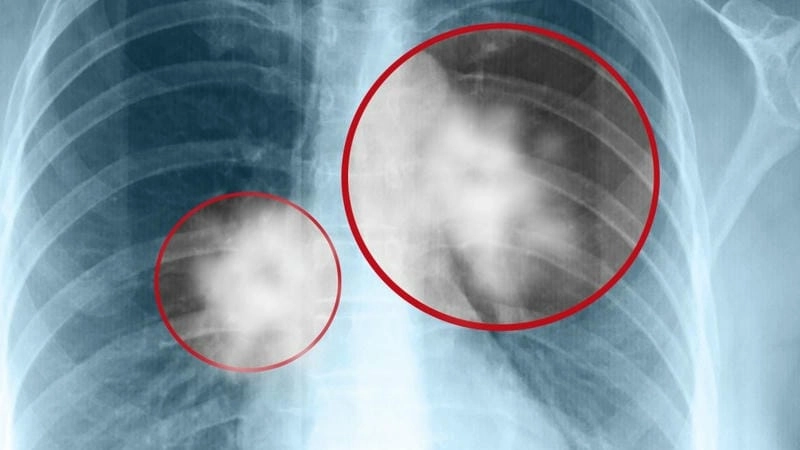

Bạn sẽ phải rùng mình khi chiêm ngưỡng hình ảnh bệnh lao phổi là như thế nào dưới ống kính y học thực tế. Những bức ảnh chụp X-quang cho thấy phổi bị tổn thương nặng, xuất hiện những đốm trắng mờ như bóng ma ám ảnh. Không chỉ là các tổn thương vật lý, đây còn là những “chứng tích sống” của căn bệnh âm thầm hủy hoại cơ thể qua từng hơi thở. Từ viêm nhẹ đến tổn thương lan rộng, hình ảnh bệnh lao phổi khiến người xem không thể rời mắt vì mức độ nghiêm trọng mà nó thể hiện rõ ràng qua từng chi tiết.

Cảnh báo: tổng hợp ảnh bệnh lao phổi chân thực này không dành cho người yếu tim. Đây là loạt hình ảnh y khoa được các chuyên gia sưu tầm và xác thực, ghi lại quá trình tiến triển của bệnh từ giai đoạn đầu đến giai đoạn nguy kịch. Từng mảng mô phổi bị ăn mòn, xơ hóa, hoại tử được phơi bày rõ nét dưới ánh sáng X-quang lạnh lùng. Những hình ảnh này không chỉ mang tính chất minh họa y học, mà còn là hồi chuông cảnh tỉnh cho bất kỳ ai còn lơ là với căn bệnh nguy hiểm này.